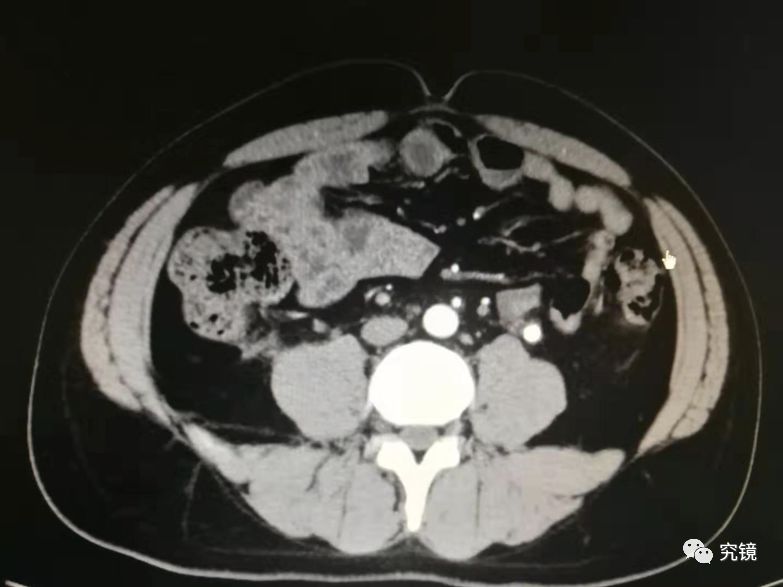

左肾积水却在右肾插管 华山医院“网红”医生参与的手术成了医疗事故左肾有病变,手术给右肾插了管江苏盐城的朱女士接受信号新闻(0532-80889431)采访时表示,她被左肾积水困扰多年,在多家医院治疗都没有获得理想的疗效。为求根治,朱女士特意到上海挂了复旦大学附属华山医院泌尿科的专家号,再次确诊“左输尿管狭窄伴左肾积水”。2021年4月19日...

江西女子长期腰痛,检查发现三个肾,医生称概率仅千分之五最近,江西新余的郑女士因长期腰痛难忍前往医院就诊,不料这检查结果让人大吃一惊,她的体内比咱们多了一个肾! CT检查显示,郑女士的的体内竟然有"三个肾",医学称之为重复肾。 新余市北湖医院泌尿外科主任袁剑:右边的肾有两个肾,这是一个肾,这下面重度积水的又是一个肾,左边是个...